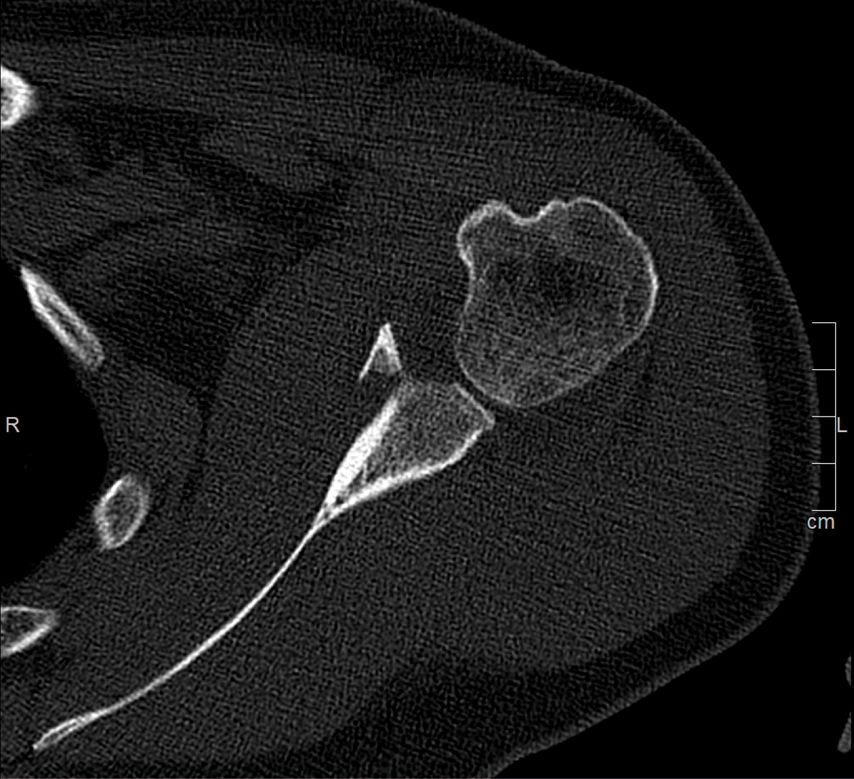

Die operative Versorgung ist indiziert bei instabilen Frakturen mit Subluxation des Humeruskopfes, großem knöchernem Defekt oder erheblichem Stufenversatz. Als Grenzwerte werden in der Literatur häufig eine Fragmentgröße von mehr als 20% der Glenoidfläche sowie ein Stufenversatz von über 5mm genannt (Itoi; Abb. 1 und 2).

Die arthroskopische Refixation hat sich als minimalinvasives Verfahren zur Versorgung selektierter Glenoidfrakturen etabliert. Insbesondere bei Ideberg-Typ-I-Frakturen (Ia ventral, Ib dorsal), knöchernen Bankart-Läsionen sowie kleinen bis mittelgroßen intraartikulären Fragmenten ermöglicht dieses Verfahren eine anatomische Rekonstruktion bei geringer Weichteilmorbidität. Voraussetzung ist das Vorliegen einer akuten Fraktur innerhalb eines Zeitraums von etwa zwei bis drei Wochen nach Trauma. Darüber hinaus müssen die Frakturfragmente reponierbar und von ausreichender Größe für eine stabile Fixation sein, während ausgedehnte Trümmerfrakturen oder eine relevante Schädigung des Skapulahalses ausgeschlossen sein sollten. Relative Kontraindikationen sind ausgeprägte Impressionen, chronische Frakturen mit Fragmentresorption sowie multidirektionale Schulterinstabilitäten. Eine sorgfältige präoperative Planung ist essenziell und basiert auf einer Computertomografie mit dreidimensionaler Rekonstruktion. Diese ermöglicht eine präzise Analyse der Fragmentgröße, der Dislokationsrichtung sowie des prozentualen Defektanteils der Glenoidfläche. Auf dieser Grundlage erfolgt die Festlegung der operativen Strategie, insbesondere die Wahl zwischen Schraubenosteosynthese und Fadenankerrefixation sowie die Planung der Anzahl und Position der arthroskopischen Portale.